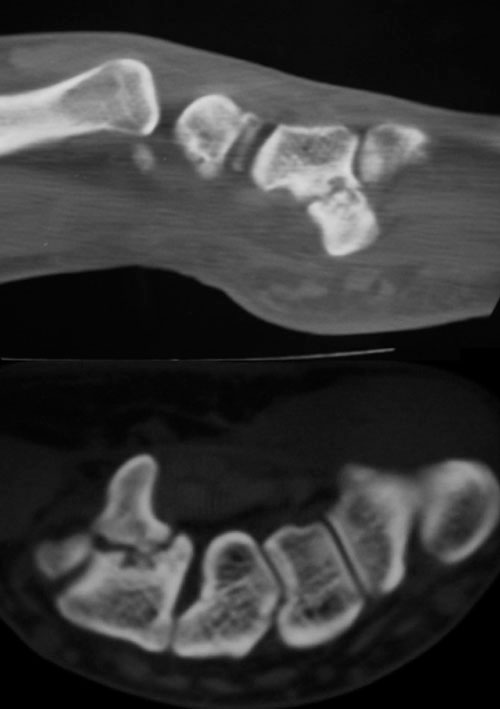

Radiografía de Fractura de la apófisis unciforme del hueso ganchoso

Figura 2: Radiografía de Fractura de la apófisis

uniforme del hueso ganchoso